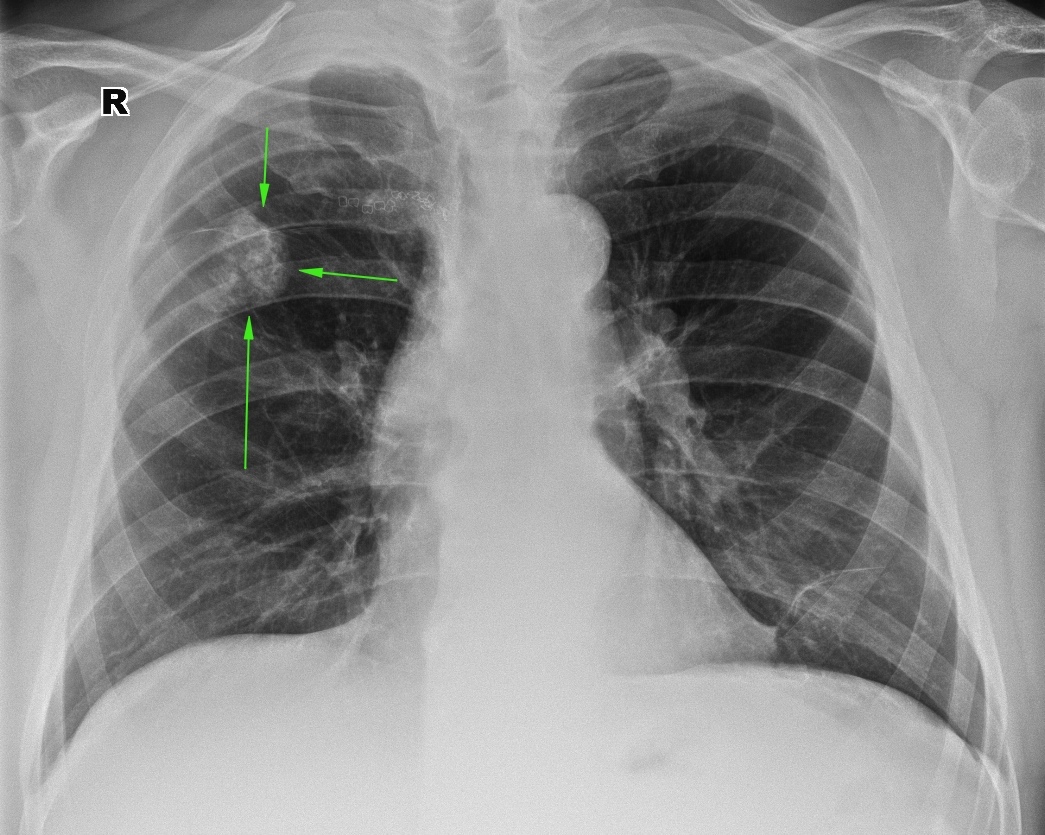

Влияние излучения при флюорографии: что нужно знать?